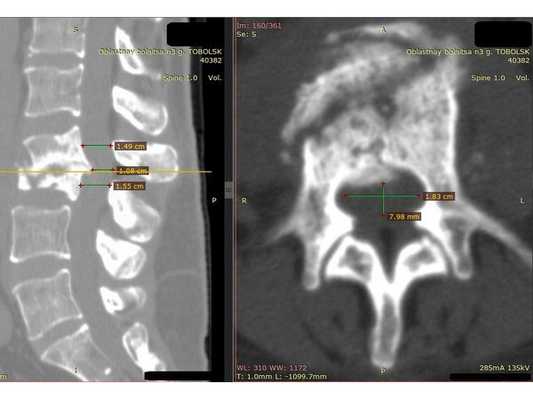

КТ пояснично-крестцового отдела позвоночника показала состояние после перенесённого спондилодисцита L2-L3 (воспалительного заболевания инфекционного характера) с разрушением тела L3 позвонка и кифотической деформацией (искривлением позвоночника) на данном уровне.

Состояние после перенесённого спондилодисцита L2, L3 позвонков с формированием абсолютного стеноза (критического сужения просвета в позвоночном столбе) на уровне L2-L3 и развитием нижнего парапареза

После операции в неврологическом статусе наблюдается положительная динамика: умеренный парапарез в нижних конечностях почти полностью регрессировал, жалобы на "онемения в ногах" также исчезли. На контрольной КТ видно состояние после успешной декомпрессии на уровне L2-L3 и установки транспедикулярной фиксирующей системы на уровне L1-L4.

Учитывая анамнез и результаты КТ пояснично-крестцового отдела позвоночника, можно предположить, что во время стационарного лечения у пациентки на уровне L2-L3 позвонков развился спондилодисцит. Характерным признаком этого заболевания в острой фазе является уменьшение рентгеновской плотности тел позвонков. Но во время проведения компьютерной томографии плотность тел L2 и L3 позвонков была высокой, что свидетельствовало о завершении воспалительного процесса и склерозировании тел позвонков. Вероятнее всего, антибактериальное лечение погасило воспаление не только в брюшной полости и почках, но и в позвоночнике. Однако после выписки из больницы, при переходе из лежачего положения в вертикальное, у пациентки стала увеличиваться кифотическая деформация. Патология привела к образованию стеноза позвоночного канала на уровне L2-L3, что и спровоцировало возникновение нижнего парапареза. С помощью транспедикулярной фиксации L1-L4 и декомпрессии на уровне L2 удалось устранить неврологические симптомы и стабилизировать позвоночный сегмент, то есть "экстренная" помощь была оказана успешно.